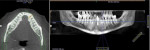

During the clinical examination, a narrow space of 3.5 mm was noted between the mandibular left lateral incisor (ie, tooth No. 23) and the right central incisor (ie, tooth No. 25) cervically. A CBCT scan was acquired to further evaluate the dimensions of the edentulous site. Using cross-sectional, coronal, and panoramic views of the site, it was determined that there was 4.5 mm between the buccal and lingual osseous limits of the space (Figure 1 and Figure 2). The adjacent incisors exhibited normal mobility, probing depths that were within normal limits, and no restorative issues. Following clinical examination and evaluation of the CBCT scan, a treatment plan was recommended that involved placing a one-piece, narrow-diameter implant that the space would accommodate, immediately placing a provisional restoration, and then fabricating and delivering a final restoration after a 4-month healing period to allow for osseointegration and soft-tissue maturation around the implant and provisional restoration. As an alternative treatment option, the patient was informed that a conventional 3-unit fixed prosthesis utilizing the adjacent natural teeth for support was also a possibility.